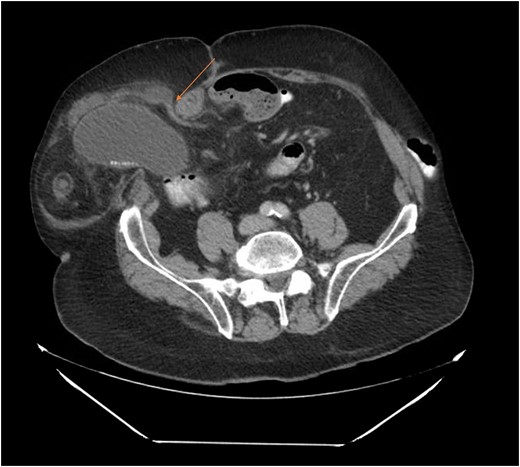

Our patient is an 89-year-old male with a history of a Hartmann’s procedure (2006) for Crohn’s disease of the sigmoid colon followed by a reversal of the colostomy with a diverting loop ileostomy (2008). Due to his comorbidities and age, the patient declined further surgery to reverse his loop ileostomy. Most recently, the patient presented to the emergency room with no ostomy output for the past 14 h, nausea and frequent burping. He reported a burning sensation around his ostomy. His physical examination revealed a large parastomal hernia in the right hemiabdomen and associated tenderness in the right upper quadrant, with no overlying skin changes. His white blood cell count was 8.1 (82.4% neutrophils), and he had normal liver function tests. A computed tomography (CT) scan of the abdomen and pelvis revealed a large parastomal hernia with a wide neck containing a distended gallbladder concerning for acute cholecystitis, as well as a small bowel obstruction with a transition point at the level of the hernia (Figs 1 and 2). A previous CT scan showed the same hernia with a nondistended gallbladder and non-obstructed bowel entering and exiting the stoma (Fig. 3).

CT from May 2017 with decompressed gallbladder and unobstructed bowel.